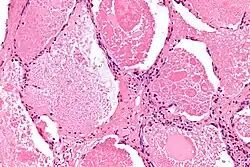

Die Alveolarproteinose wird auch als pulmonal-alveoläre Proteinose oder als Phospholipoproteinose bezeichnet. Die englische Bezeichnung lautet pulmonary alveolar proteinosis (PAP). Die Erkrankung ist selten und hat eine großenteils unbekannte Ätiologie. Es liegt eine Füllung des Alveolarraums mit zellfreiem, amorphem, eosinophilem, lipidreichem Material vor, bedingt durch eine Störung des Surfactantmechanismus. Männer erkranken häufiger als Frauen, meist im mittleren Erwachsenenalter. Die Erkrankung kann klinisch unerkannt auftreten, Spontanremissionen sind möglich. Sie tritt kongenital, im Kindesalter, oder auch im mittleren Erwachsenenalter auf.

Tumormarker und Surfactant-Merkmale sind in spezifischen Mustern verändert. Im Schauglas zeigt bronchoalveoläre Lavage eine milchig-trübe Flüssigkeit mit PAS-positivem Sediment, was mit seiner Mehrlagigkeit ein typisches Merkmal ist.